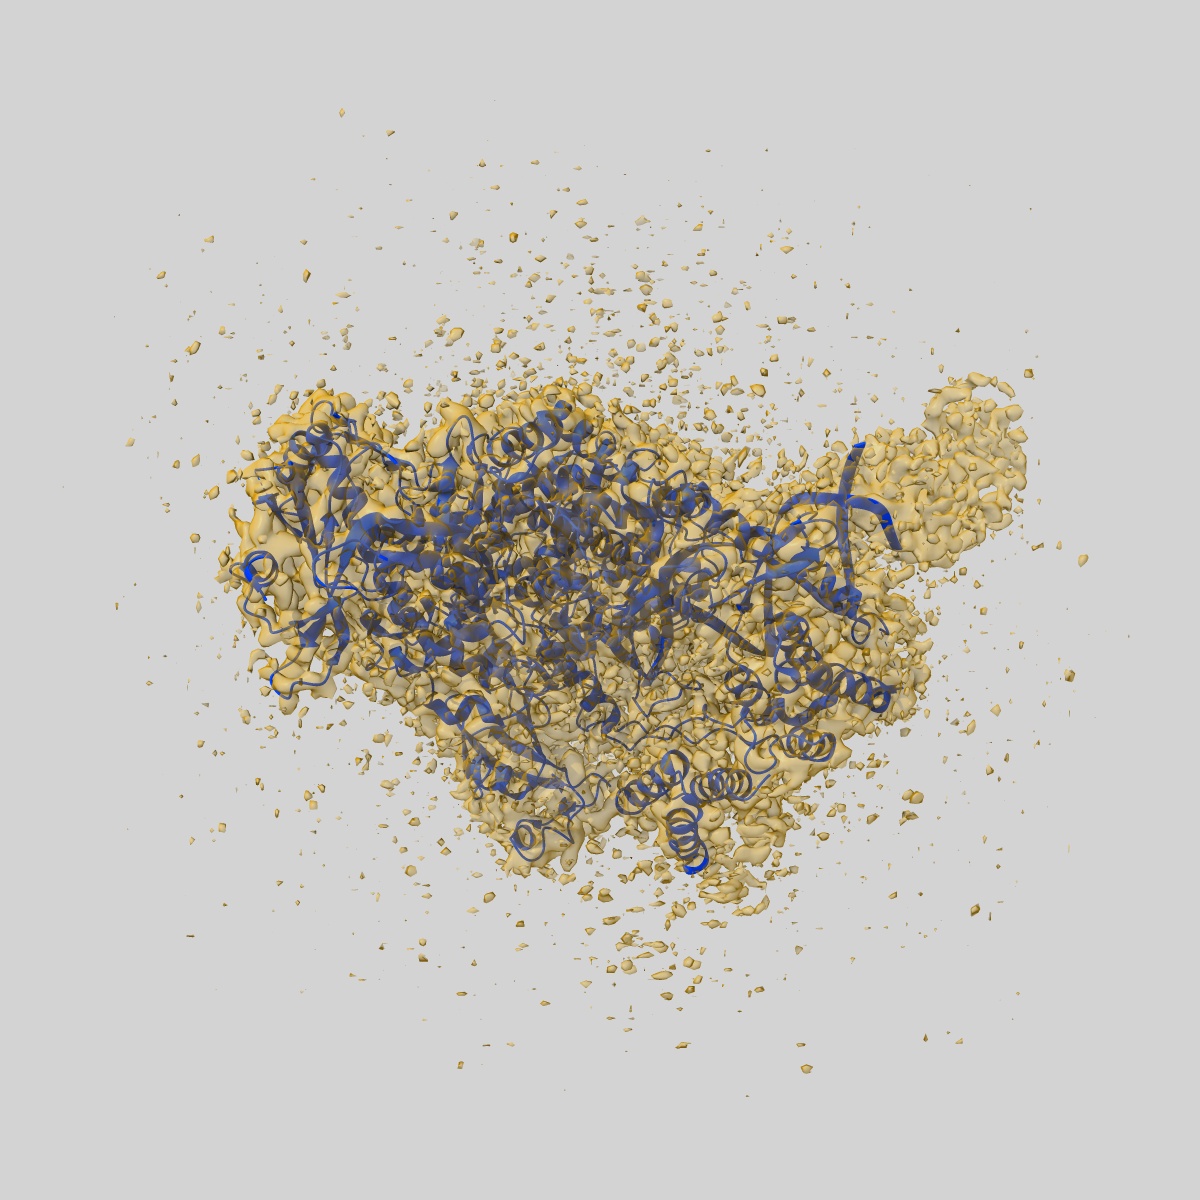

Cryo-EM structure of SARS CoV-2 RdRp wild-type in complex with 20-40mer RNA incorporating ATP

Sample: SARS CoV-2 RdRp wild-type in complex with 20-40mer RNA incorporating ATP

Fitted models: 9sar

Structural basis for selective remdesivir incorporation by SARS-CoV-2 RNA polymerase, and S759A resistance.

Gordon CJ, Oliva MF, Lee HW, Goovaerts Q, De Wijngaert B, Gotte M, Das K

(2025) bioRxiv